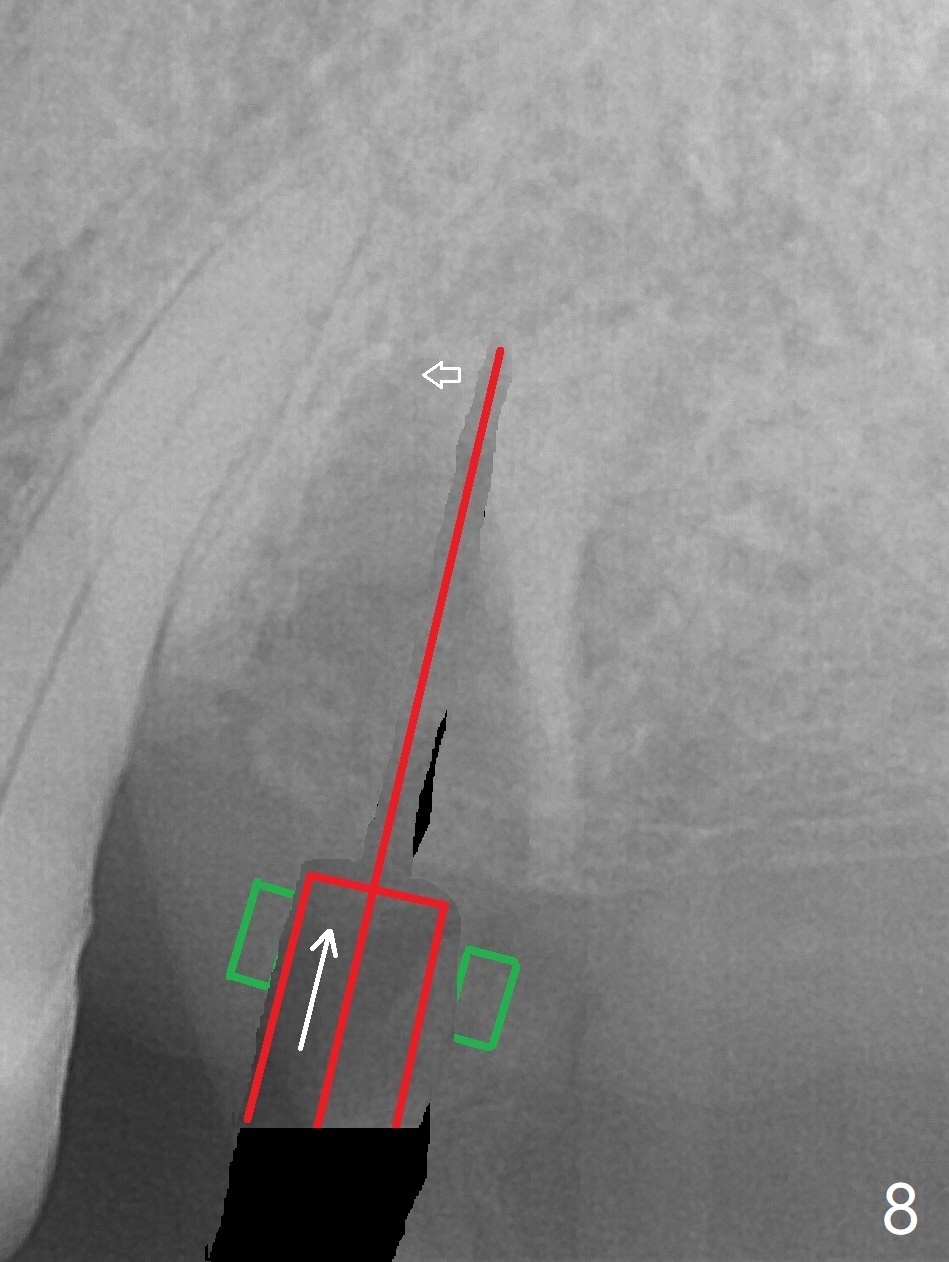

After extraction of the tooth #13 residual root, the bone in the distal wall of the socket looks white. Intraop PA rules out root structure (Fig.1 *). Osteotomy is conducted according to drill sequence. Bitewings are taken to check implant placement level (Fig.2,3). Following implant level adjustment and healing abutment installment (Fig.4,5 (*: bone graft)), the implant at #13 is found to be close the root of #12 (Fig.6 *), i.e., not parallel to the implant at #14. Introspectively, 2.2x10 mm drill seems to be long. When it touches the bone, the cylinder portion of the drill (Fig.7 red) does not engage into the sleeve (green). When it goes into the bone, it may have been deflected mesial due to the slope of the distal wall of the socket (hard bone, Fig.8 open arrow)). If a shorter drill (such as 2.2x7.3 or 8.5 mm) were used (Fig.9), the deflection would be minimal if drilling is slow (Fig.10). CT taken 1 week postop shows that the implant at #13 is approximately 1 mm near the root of the tooth #12, but the neurovascular bundle to the latter seems not to have been interrupted (Fig.11,12). The buccopalatal trajectory at #14 is within normal limit (Fig.11,13 (B: buccal)). There is no periapical radiolucency at #12 five months postop (Fig.14). However the cemented abutments are incompletely seated (<). The patient is reluctant to return for impression 17 months postop (due to coronavirus); with attention, the same abutment at #13 is reseated completely; an abutment with longer cuff and narrower diameter is also seated completely (Fig.15).